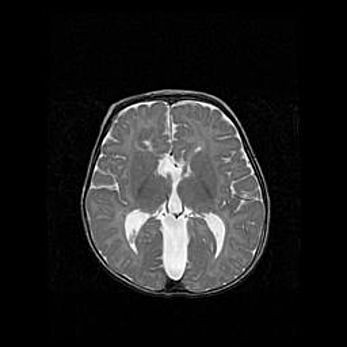

Лейкомаляция с кистозно-глиозной дегенерацией головного мозга.

Возраст: 2 месяца 25 дней

Вес: 6400 г

Окружность головы: 40 см

Срок гестации: 41 неделя

Лейкомаляцию относят к ишемически-гипоксическим повреждениям головного мозга, диагностируемым у новорожденных. При лейкомаляции в головном мозге обнаруживают очаги некроза, возникшие после тяжелой гипоксии и нарушения кровотока. В процессе морфогенеза очаги проходят три стадии: 1) развития некроза, 2) резорбции и 3) формирования глиозного рубца или кисты. Перивентрикулярная лейкомаляция (ПЛ) встречается примерно в 12% случаев среди новорожденных, обычно – у недоношенных детей, причем, частота ее зависит от массы, с которой младенец появился на свет. Наибольшее число малышей страдает лейкомаляцией, если масса при рождении 1500-2500 г.